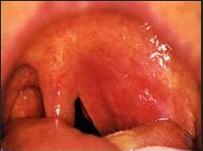

从检查上可见病人很痛苦,张口受限,头歪,流口水;咽粘膜充血明显,患侧软腭充血显著,悬雍垂水肿,常被推向对侧;脓肿常见于扁桃体上极与舌腭弓之间,该处明显隆起,触之病人会感到剧痛,穿刺可抽出脓性分泌物。

上图:左侧扁桃体周围脓肿形成